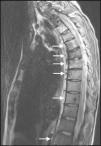

After delivery, the patient underwent a thoracoabdominal CT which depicted a large left hilar mass with no plane of cleavage with vascular structures, multiple implants on mediastinal pleura, and a large volume of left pleural effusion (Fig. 1B), and multiple bone and liver metastases. First line chemotherapy with carboplatin plus oral vinorelbine (AUC 5 and 60mg/m2, respectively) was started on September 2010. Intravenous zoledronic acid was also prescribed. After 4 sessions of chemotherapy, despite some clinical improvement, there was progression of the disease with the spreading of bone disease and neurological symptoms of paraplegia and sphincter disruption (Fig. 2). Subsequently, the patient underwent second line chemotherapy with pemetrexed (500mg/m2), and thoracic spine (T4–T10) radiotherapy (30Gy/12 sessions), but without clinical efficacy.

An EML4-ALK translocation (FISH method) was then identified in an additional genetic test and crizotinib 250mg BID was started on March 2011. The patient showed global symptom relief and improvement of neurological signs, and also partial radiological response (Fig. 3) based on RECIST criteria. She showed only mildly elevated hepatic transaminases, without other adverse effects. Her progression-free survival was 9 months and she died 19 months after diagnosis.